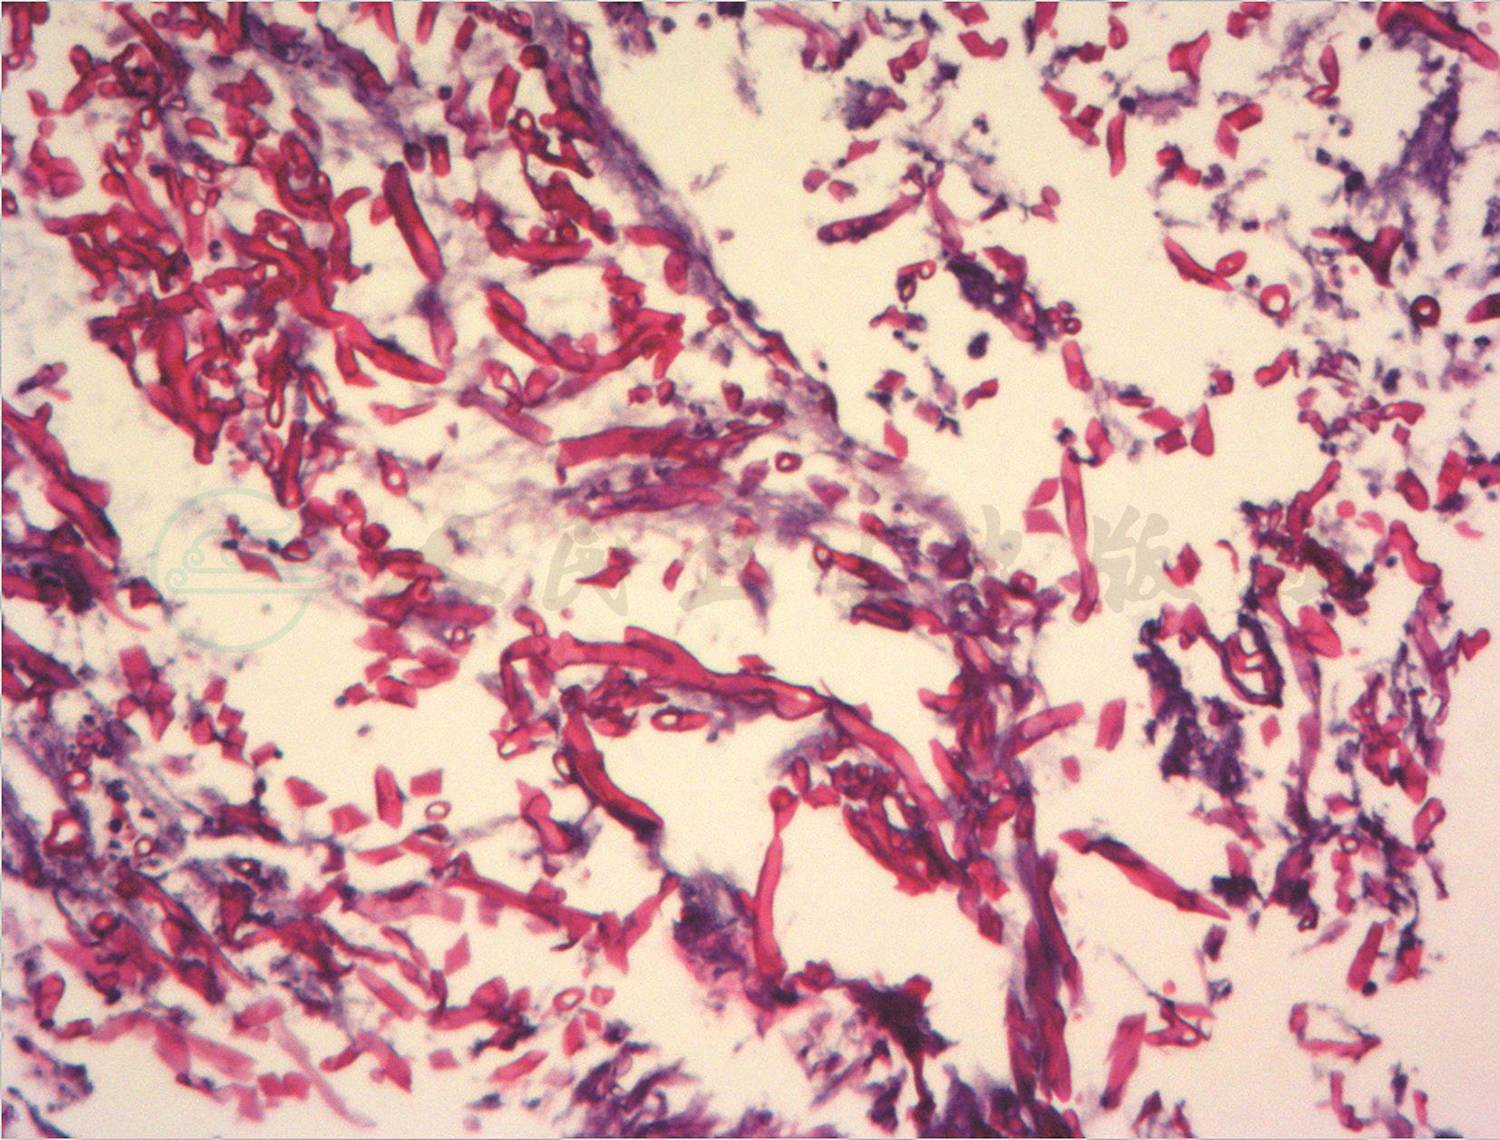

转入笔者科室立即完善相关病原学检查提示GM试验阴性,1,3-β-D葡聚糖 <10µg/L,痰培养及血培养均阴性,PPD 阴性,结核斑点试验(T-spot)阴性,以上检查均未找到明确病原体。入院第5天完善纤维支气管镜检查,镜下示(图3)右肺下叶B10亚段可见大量黄白色类干酪样物质阻塞及坏死黏膜附着管壁,予毛刷刷检,刷检时黏膜有出血,予万分之一盐酸肾上腺素冲洗止血,将刷检物质送病理检查。根据镜下改变,高度怀疑支气管内膜结核及真菌感染。经胸科医院会诊,建议诊断性抗结核治疗,但家属拒绝。给予患儿伏立康唑抗真菌治疗,7天后体温恢复平稳,无咯血,复查肺CT(图4)提示右肺下叶后底段支气管旁高密度团块影较前减小。入院第12天病理结果回报(图5)提示炎性渗出坏死物及霉菌。

图5 支气管镜下病理结果